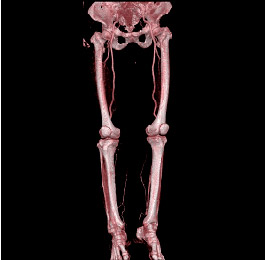

| 足の血管(正面の画像) | 足の血管(背面の画像) |

その結果、単に画像が速く綺麗に撮れるということにとどまらず、従来はできなかった縦方向の画像(実際に撮影しているのではなく、検査後にコンピュータで計算させて

上下方向の画像を作成するもの:MPR画像という)や、立体的な3次元画像なども従来よりもはるかに有用なものとして活用できるようになっております。